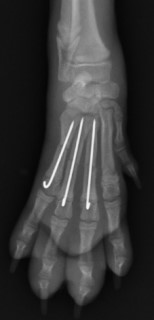

手術前 手術後

ピンニングで整復しました。